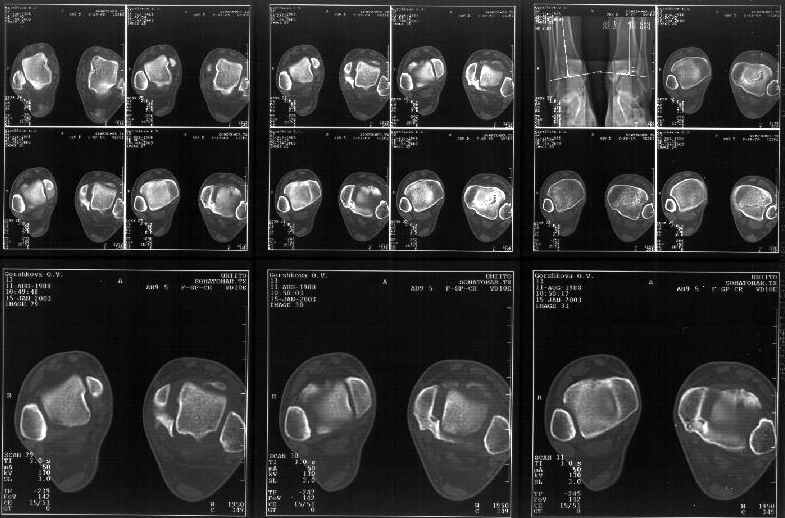

Сегодня пациентке сделали сравнительную КТ. А ксиальные и Фронтальные срезы приложены. Ваше мнение?

Фронтальные

Аксиальные